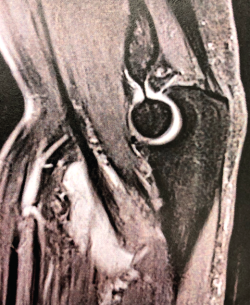

Las lesiones del tendón distal del bíceps varían desde la bursitis bicipitorradial hasta las roturas completas, pasando por las tendinosis y las lesiones parciales. Una buena historia clínica y una exploración física meticulosa aportan gran cantidad de información a la hora de orientar el diagnóstico, que se puede apoyar en la ecografía y la resonancia nuclear magnética para confirmar el diagnóstico y descartar otras entidades plausibles. En el caso de la bursitis bicipitorradial, la tendinosis y las lesiones parciales, el tratamiento inicial debe ser conservador salvo en casos concretos. Las roturas completas agudas deben tratarse de forma quirúrgica excepto en pacientes con baja demanda física o no aptos para tratamiento quirúrgico, sin sobrepasar las 4 semanas de evolución. En caso de diagnóstico tardío y roturas crónicas, las alternativas son la reparación primaria o la reconstrucción con autoinjerto o aloinjerto. Tras la cirugía, es imprescindible seguir un protocolo de rehabilitación que progrese en la ganancia del balance articular y la fuerza sin alterar el proceso de cicatrización. El objetivo de este artículo es presentar las distintas lesiones del bíceps distal, los métodos diagnósticos más adecuados y las alternativas terapéuticas para cada una de las entidades patológicas, para lo que se ha llevado a cabo una revisión bibliográfica a través del motor de búsqueda PubMed de artículos en inglés con referencia al tema seleccionado.

Distal biceps tendon injuries vary from bicipitoradial bursitis to complete rupture, including tendinosis and partial rupture. A good patient history and physical examination provide a great amount of information when trying to establish diagnosis helped by ultrasound and MRI to confirm our suspicion and make a differential diagnosis. Initial treatment for bicipitoradial bursitis, tendinosis and partial rupture should be conservative except in some concrete patients. Complete acute ruptures should be managed by surgical treatment except in low demand patients or patients with concerns regarding anesthesia or surgery. This surgery should be performed before 4 weeks after initial trauma. In case of delayed diagnosis or chronic ruptures, the different alternatives are primary reparation or reconstruction with autograft or allograft. After surgery a rehabilitation program is essential to improve range of motion and strength without stressing the healing process. The main purpose of this manuscript is to present different distal biceps injuries, the most adequate ways to establish a diagnosis and treatment alternatives for every kind of lesion. That is why a revision has been performed through PubMed search engine regarding the selected issue.